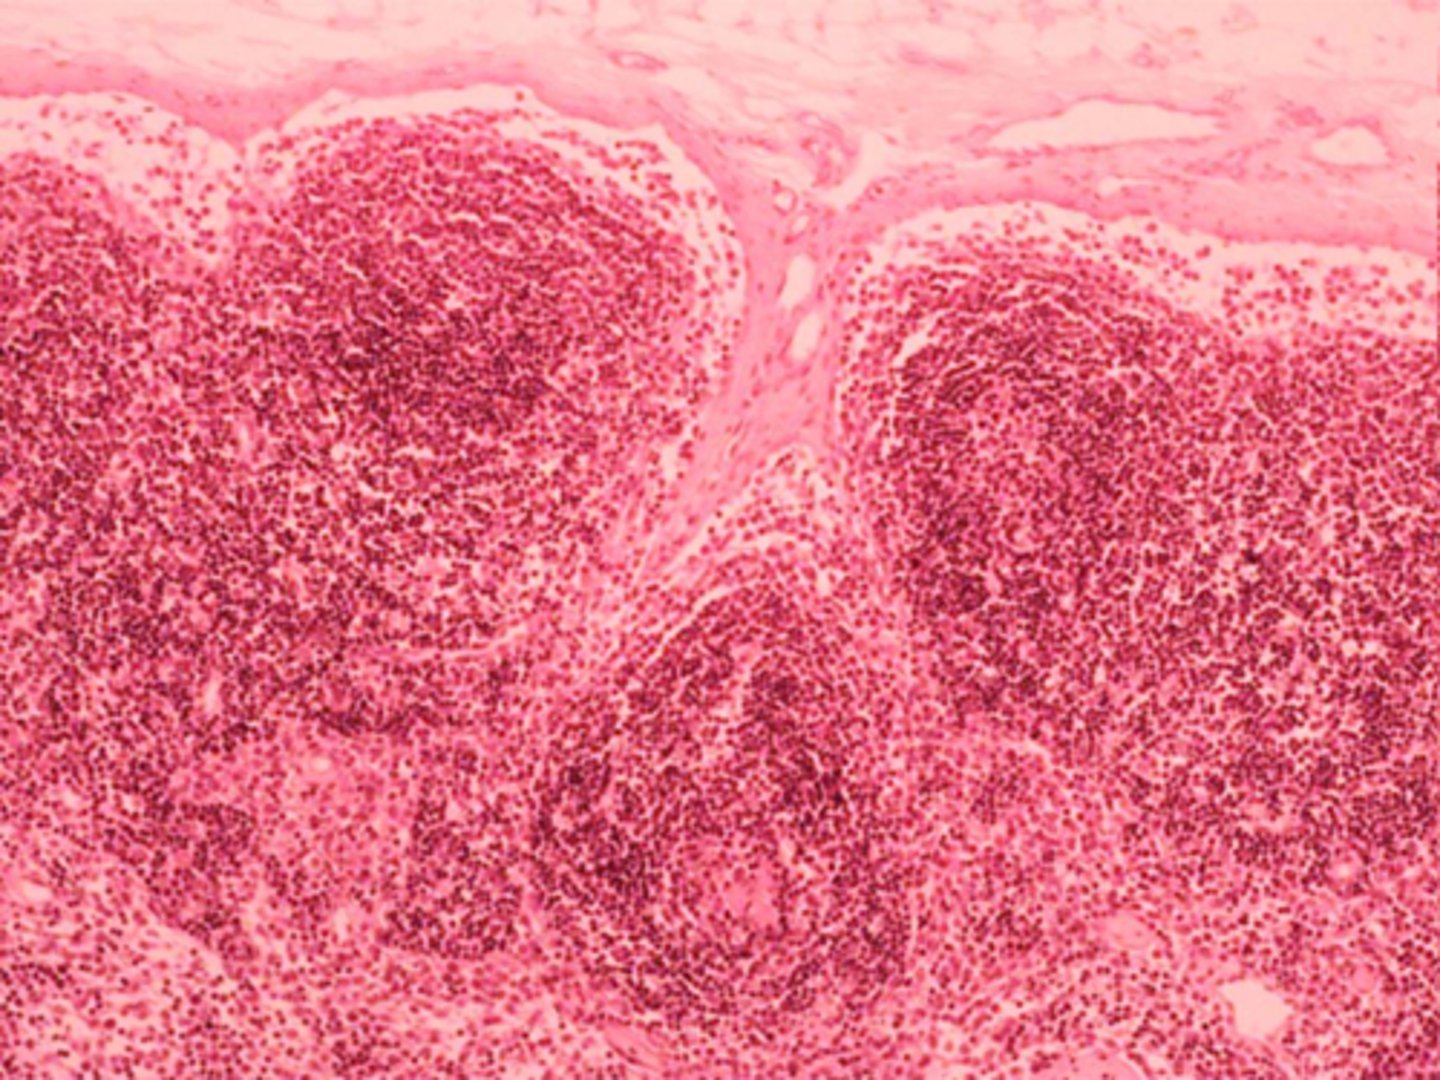

primary lymphatic nodule (made of B lymphocytes)

black arrow

T lymphocytes

red arrow

colon: lymphoid nodule

where is this tissue located?

B lymphocytes

(not exposed to pathogen yet)